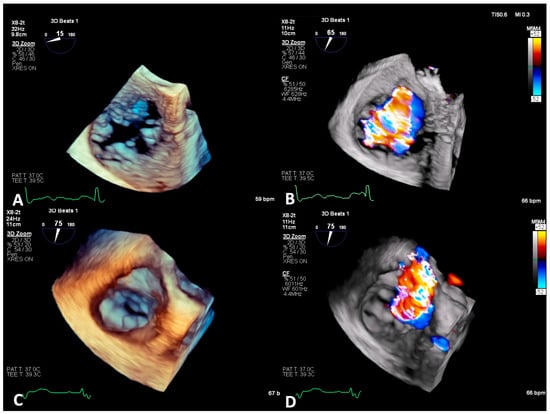

6.1. TEE-Guided Tricuspid TEER